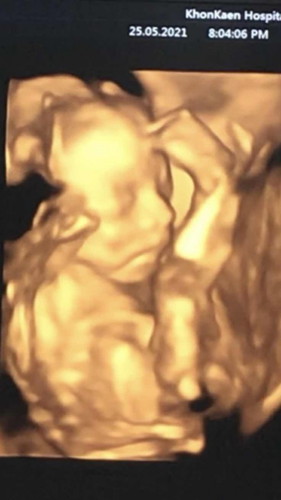

1ตุลาจ้า ไปซาวแล้ว น้องหนีบไม่ให้ดูเลยจ้า แม่ต้องลุ้นต่อไปจ้า

แม่ซาวน้องกี่วีคค่ะ บ้านนี้หมอบอก28wถึงซาว4มิติได้

19 w จ้า.

ท่าเดียวกันเลยค่ะ ลูกสาวเหมือนกันค่ะ 17w